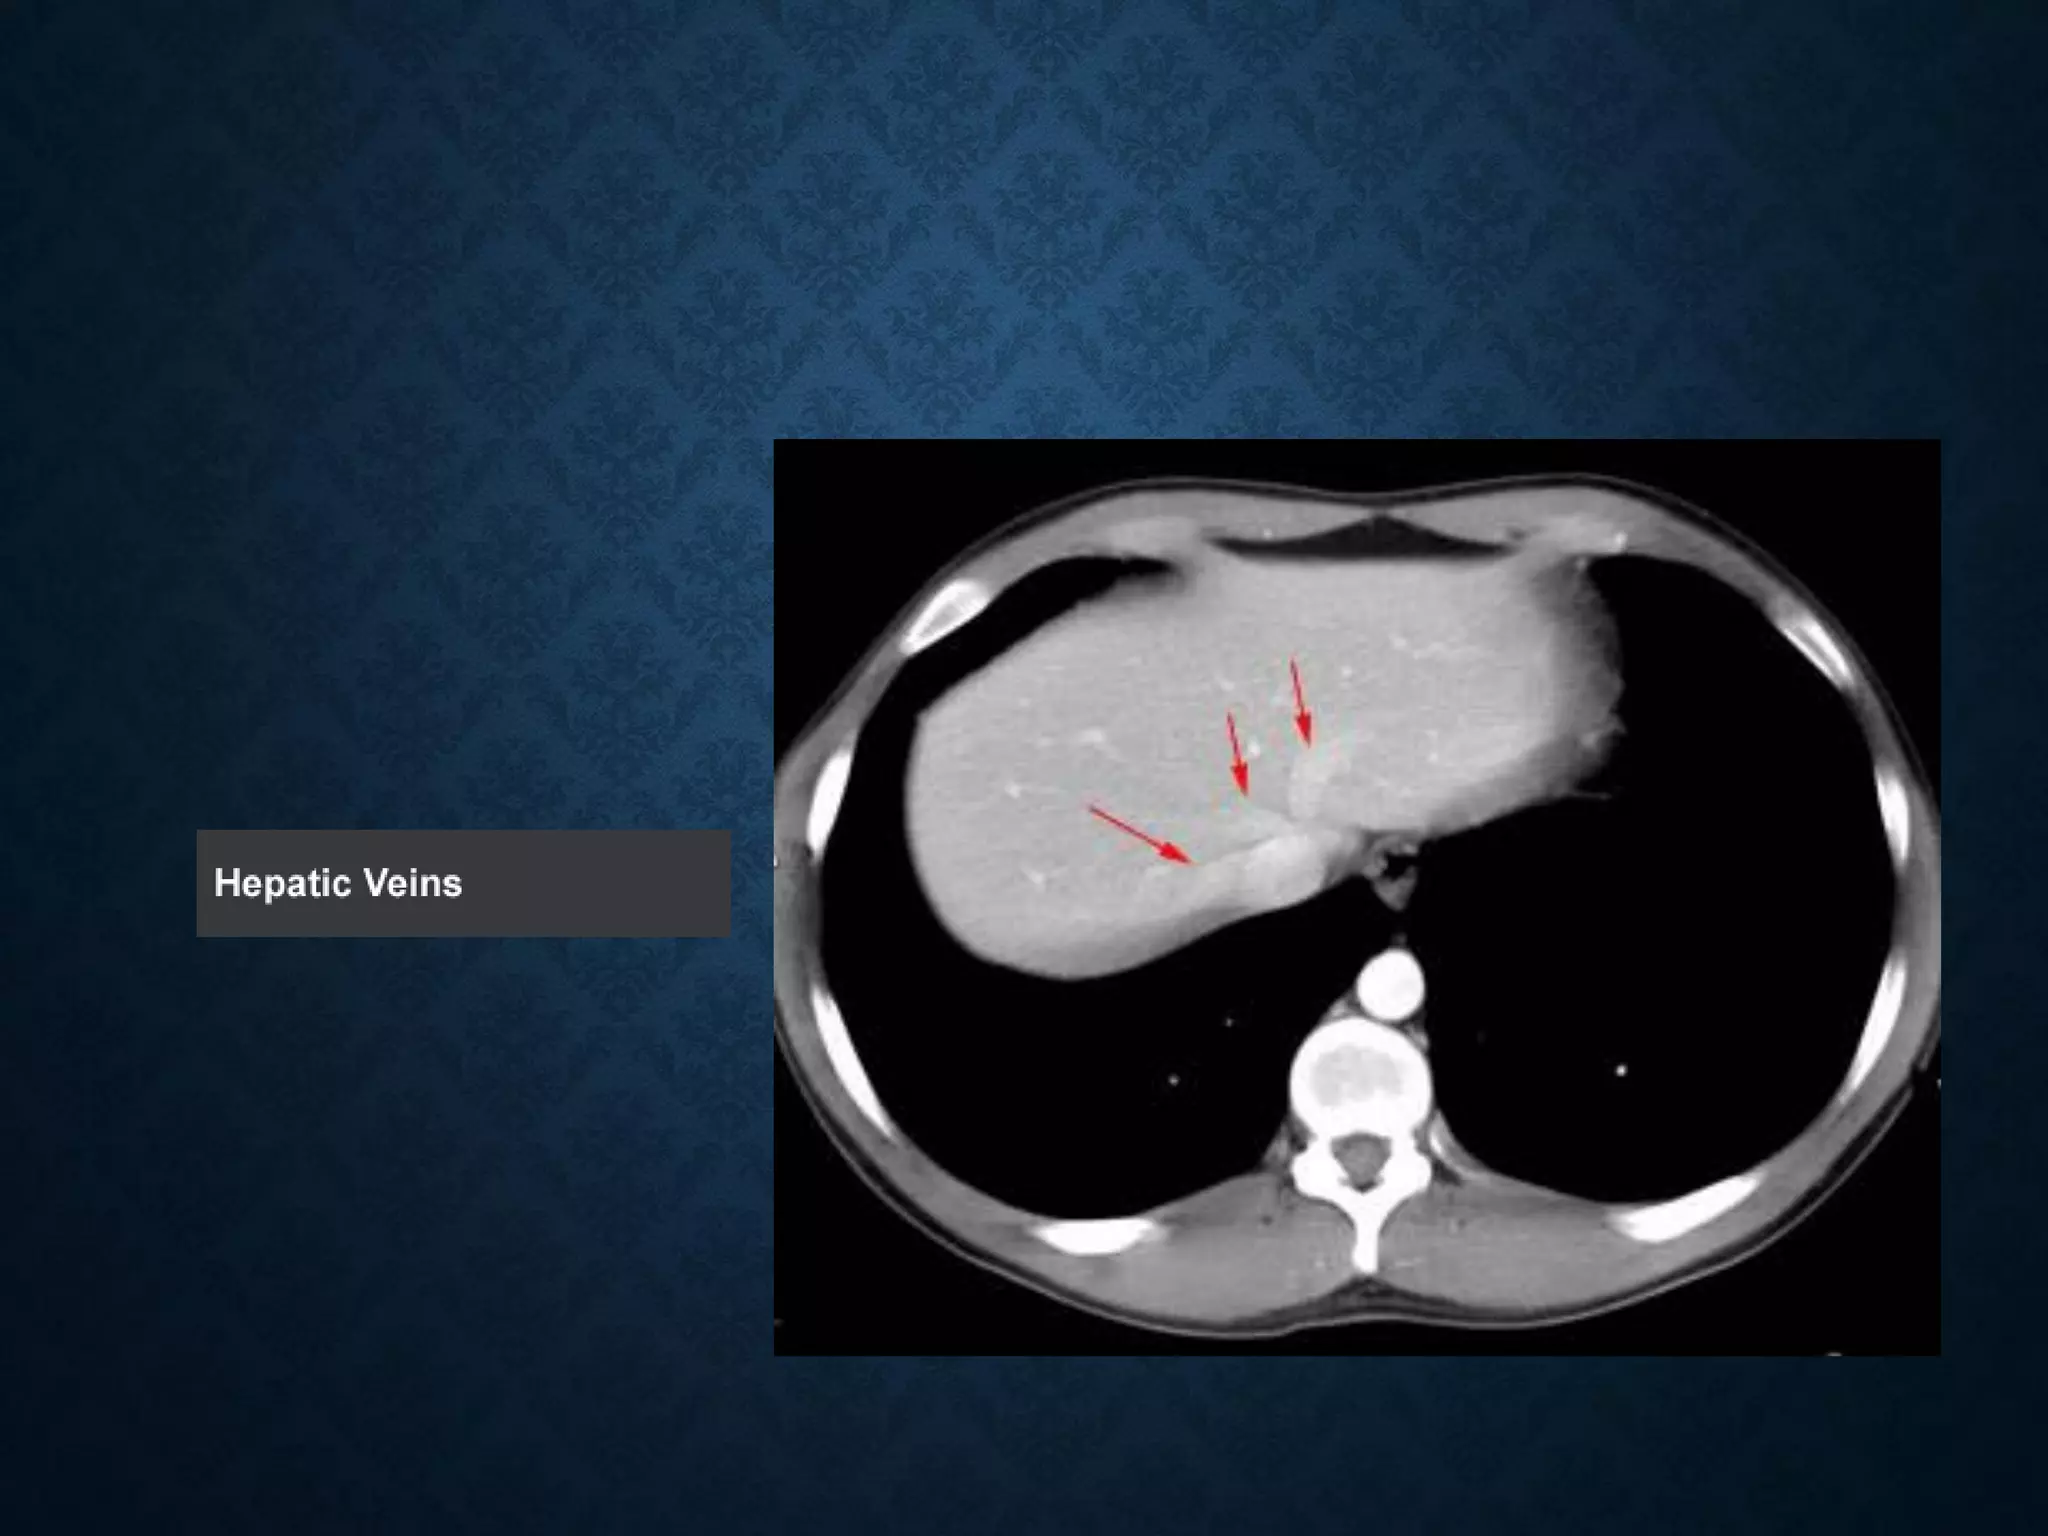

Identify the following structures in the body CT to the right. To view the location of the structure in the image click on

the label at the left and the structure will be indicated in the image. Abdominal CT scans typically begin just above

the diaphragm, so the first slice you see is of the lower chest.